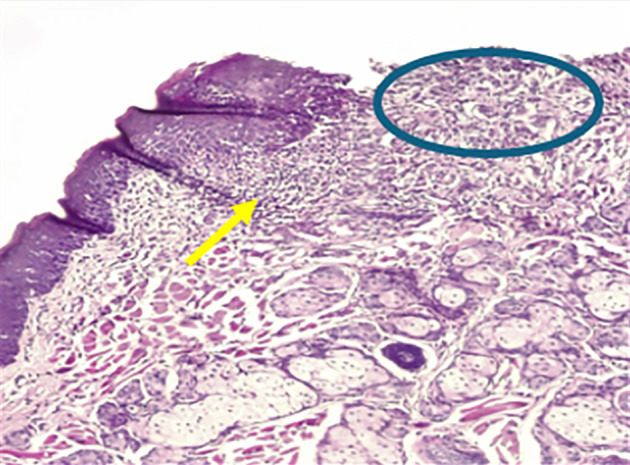

Materials and methods: Sixty-six adult male rats with a chemically induced ulcer in the buccal mucosa. The animals were distributed randomly into two groups: a control group that had not received any treatment and a test group that was treated with topical ROE 3 times per day for 10 days. The samples were obtained on day 3, day 7, and day 10, and then the tissue staining was done using hematoxylin and eosin (H&E) and histomorphometric analysis.

Results: The findings of this study demonstrated from cellular investigations that 20 mg/mL ROE can efficiently stimulate HGF proliferation at 24, 48, and 72 h. The animal study results revealed that ROE could substantially boost the healing of the induced ulcer model by lowering the inflammatory cells and extensively promoting collagen formation within the ulcer site on days 3 and 7.